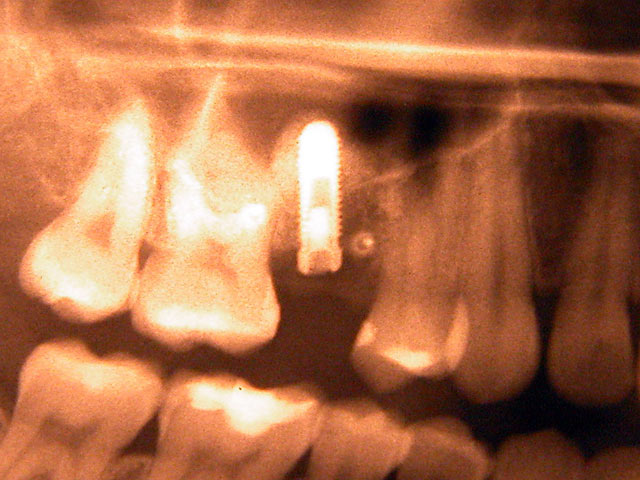

Kurzimplantate und Sofort – Implantate: